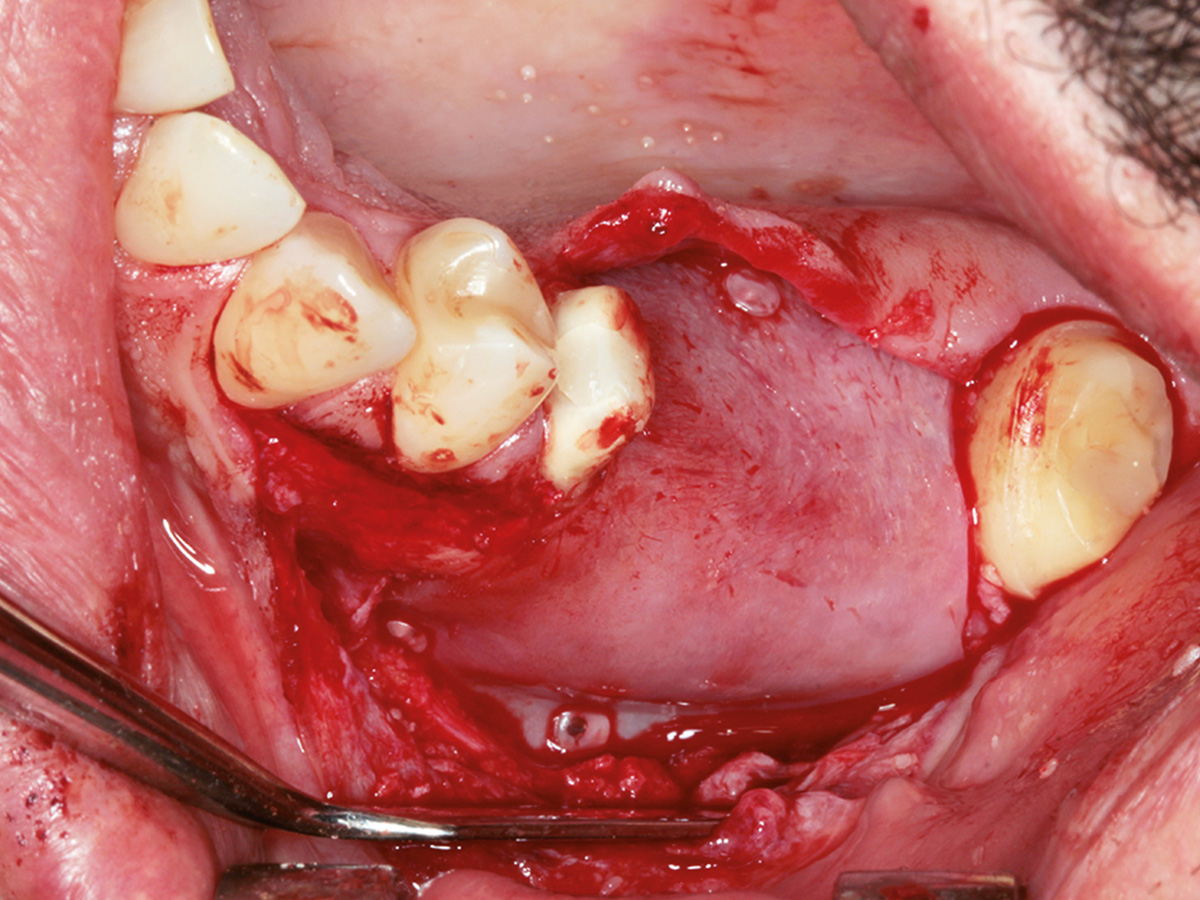

In diesem Kurs wird das Handling mit der Bone Lamina samt Augmentation geübt. Danach sollte jeder Teilnehmer inder Lage sein, im Praxisalltag Knochen aufzubauen. Dazu isteine korrekte Schnittführung notwendig, die ebenfalls thematisiert wird. Damit ein Knochenaufbau erfolgreich einheilt, ist der spannungsfreie Wundverschluss zwingend erforderlich.Deshalb wird im Kurs auch besonderes Augenmerk auf spezielle Nahttechniken gelegt, die am Modell und am Schweinekiefer geübt werden.